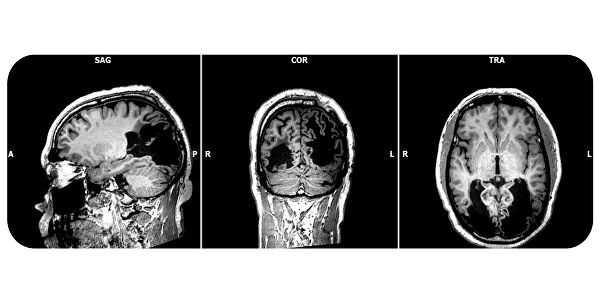

Мозг пациента, ослепшего после инсульта. Темным цветом обозначены повреждения в первичной зрительной коре. В экспериментах этот пациент, несмотря на слепоту, по размеру фигуры предугадывал, когда звук будет увеличиватьсяДело в том, что нижние бугорки обычно отвечают за обработку звуковых стимулов, а в верхних заканчивается часть волокон зрительного нерва и происходит быстрая обработка данных, полученных от сетчатки. Это позволяет убежать от приближающейся угрозы — например, хищника — еще до того, как организм поймет, что происходит. Из верхних бугорков четверохолмия информация поступает в таламус, а затем сразу во вторичную зрительную кору.Судя по всему, это сохраняется у пациентов с повреждениями первичной зрительной коры. Поэтому они и различают лица, способны огибать препятствия.Химики из МГУ разгадали тайну «невозможно быстрой» работы рецепторов глазБолее того, формируются сложные зрительно-слуховые ассоциации, когда слепой соотносит звук с размером предмета. Исследователи просили добровольца с поврежденной стриарной корой нажимать на кнопку, если ему кажется, что звуки должны усилиться. На экране перед ним находился красный кружок, который резко уменьшался перед тем, как прибавляли громкость. Слепой раз за разом при сжимании круга все быстрее нажимал на кнопку. Значит, в его мозгу возникала причинно-следственная связь между громкостью звука и размером фигуры, хотя он ее не видел.Авторы работы считают, что благодаря этому механизму люди, ослепшие из-за травмы, могут восстановить некоторые зрительные навыки и даже обучаться чему-то новому.